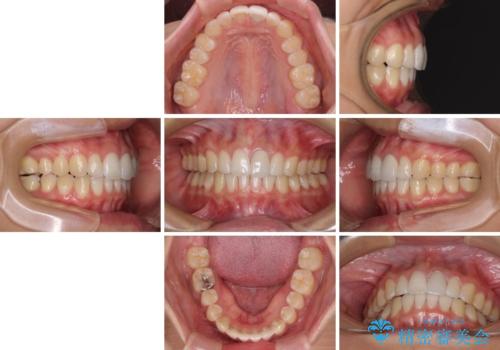

気になる前歯を治したい インビザライン矯正とオールセラミッククラウン

- 変色した前歯と突出した口元を気にして来院された患者様です。

口元の突出感はインビザラインにより歯列を整え、その後に、前歯をオーダーメイドタイプのオールセラミッククラウンにて補綴治療することとしました。

長時間のマウスピース装着と、患者様自身でのゴムかけに協力いただき、口元の突出感をしっかりと改善することができました。

前歯のオールセラミッククラウンもまるで本物の歯のように仕上がり、患者様には大変満足していただきました。